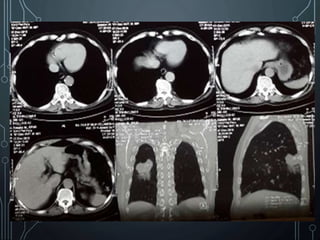

CT SCAN THORAX TANPA KONTRAS

• CT scan thorax tanpa kontras irisan axial

reformat coronal dan sagittal :

-Tampak perselubungan pada paru

kanan posterior, tepi tidak rata,

berukuran sekitar

3x4cm

-Pembesaran KGB peribronchial kanan

-Paru kiri normal, nodul (-), hilus normal

-Cor normal

-Trachea, main bronchus bebas

Kesan : Tumor paru kanan, DD/ pneumonia,

disertai